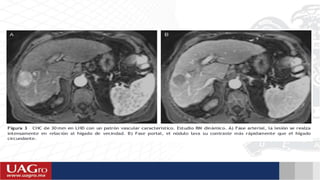

Técnicas de diagnostico : US con contraste, TC multifasica, RM dinámica.

 Lineamientos según AASLD : Lesión >1cm/Dm con hipervascularidad y lavado venoso tardío cumple con

los criterios para ser diagnosticada como CHC y no requiere biopsia.

 Criterios de la EASL : Existencia de 2 métodos de imagen que concuerden en dicha apreciación de una

lesión focal > 2cm que muestre hipervascularidad y un nivel de AFP >400ng/ml es diagnostico de CHC.